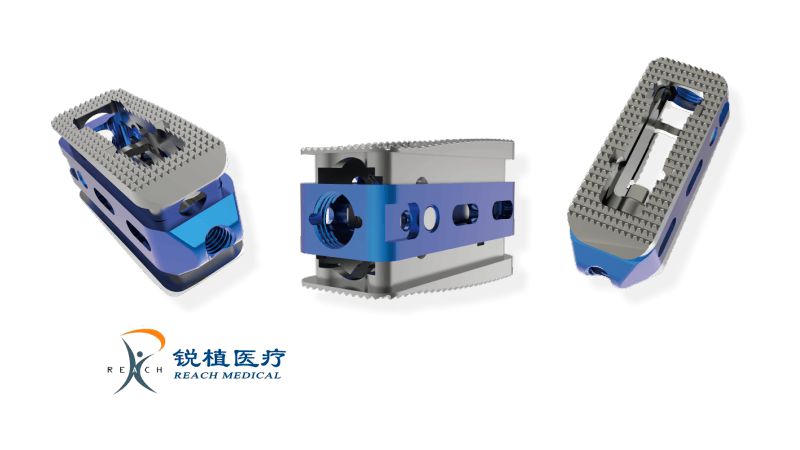

Hanfuse é um dispositivo estéril de fusão lombar expansível (8–13 mm) para distração controlada e ajuste às placas terminais, indicado no tratamento da doença degenerativa do disco entre L2–S1 (1–2 níveis).

Aplicável para as abordagens: PLIF, TLIF, MISS-TLIF e ENDOLIF.

DIFERENCIAIS

- Produzido em 100% titânio C4

- Expansão contínua e controlável para restauração precisa do espaço intervertebral

- Superfícies em dente invertido que otimizam o encaixe nas placas terminais

- Ponta em formato bullet para facilitar a implantação